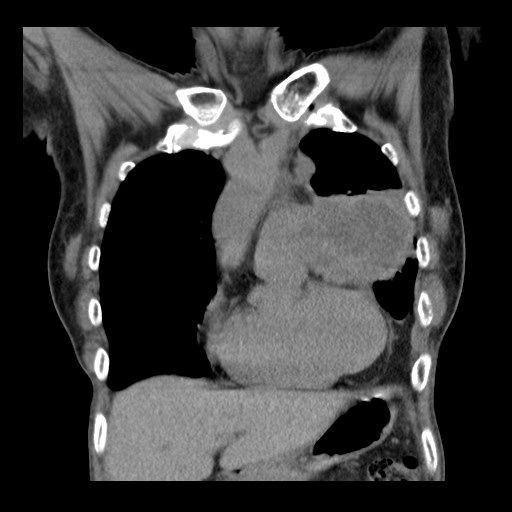

蘇一峰透露,該婦人接受X光檢查後,發現肺腫瘤已長達7、8厘米,已不能開刀做手術。對此,他不禁嘆道:「台灣女性忍耐力很強,肺癌等到有症狀常常都是末期。在台灣定期檢查肺癌真的非常需要,不能等到有症狀才來看醫師(生)......」

May be an image of xray